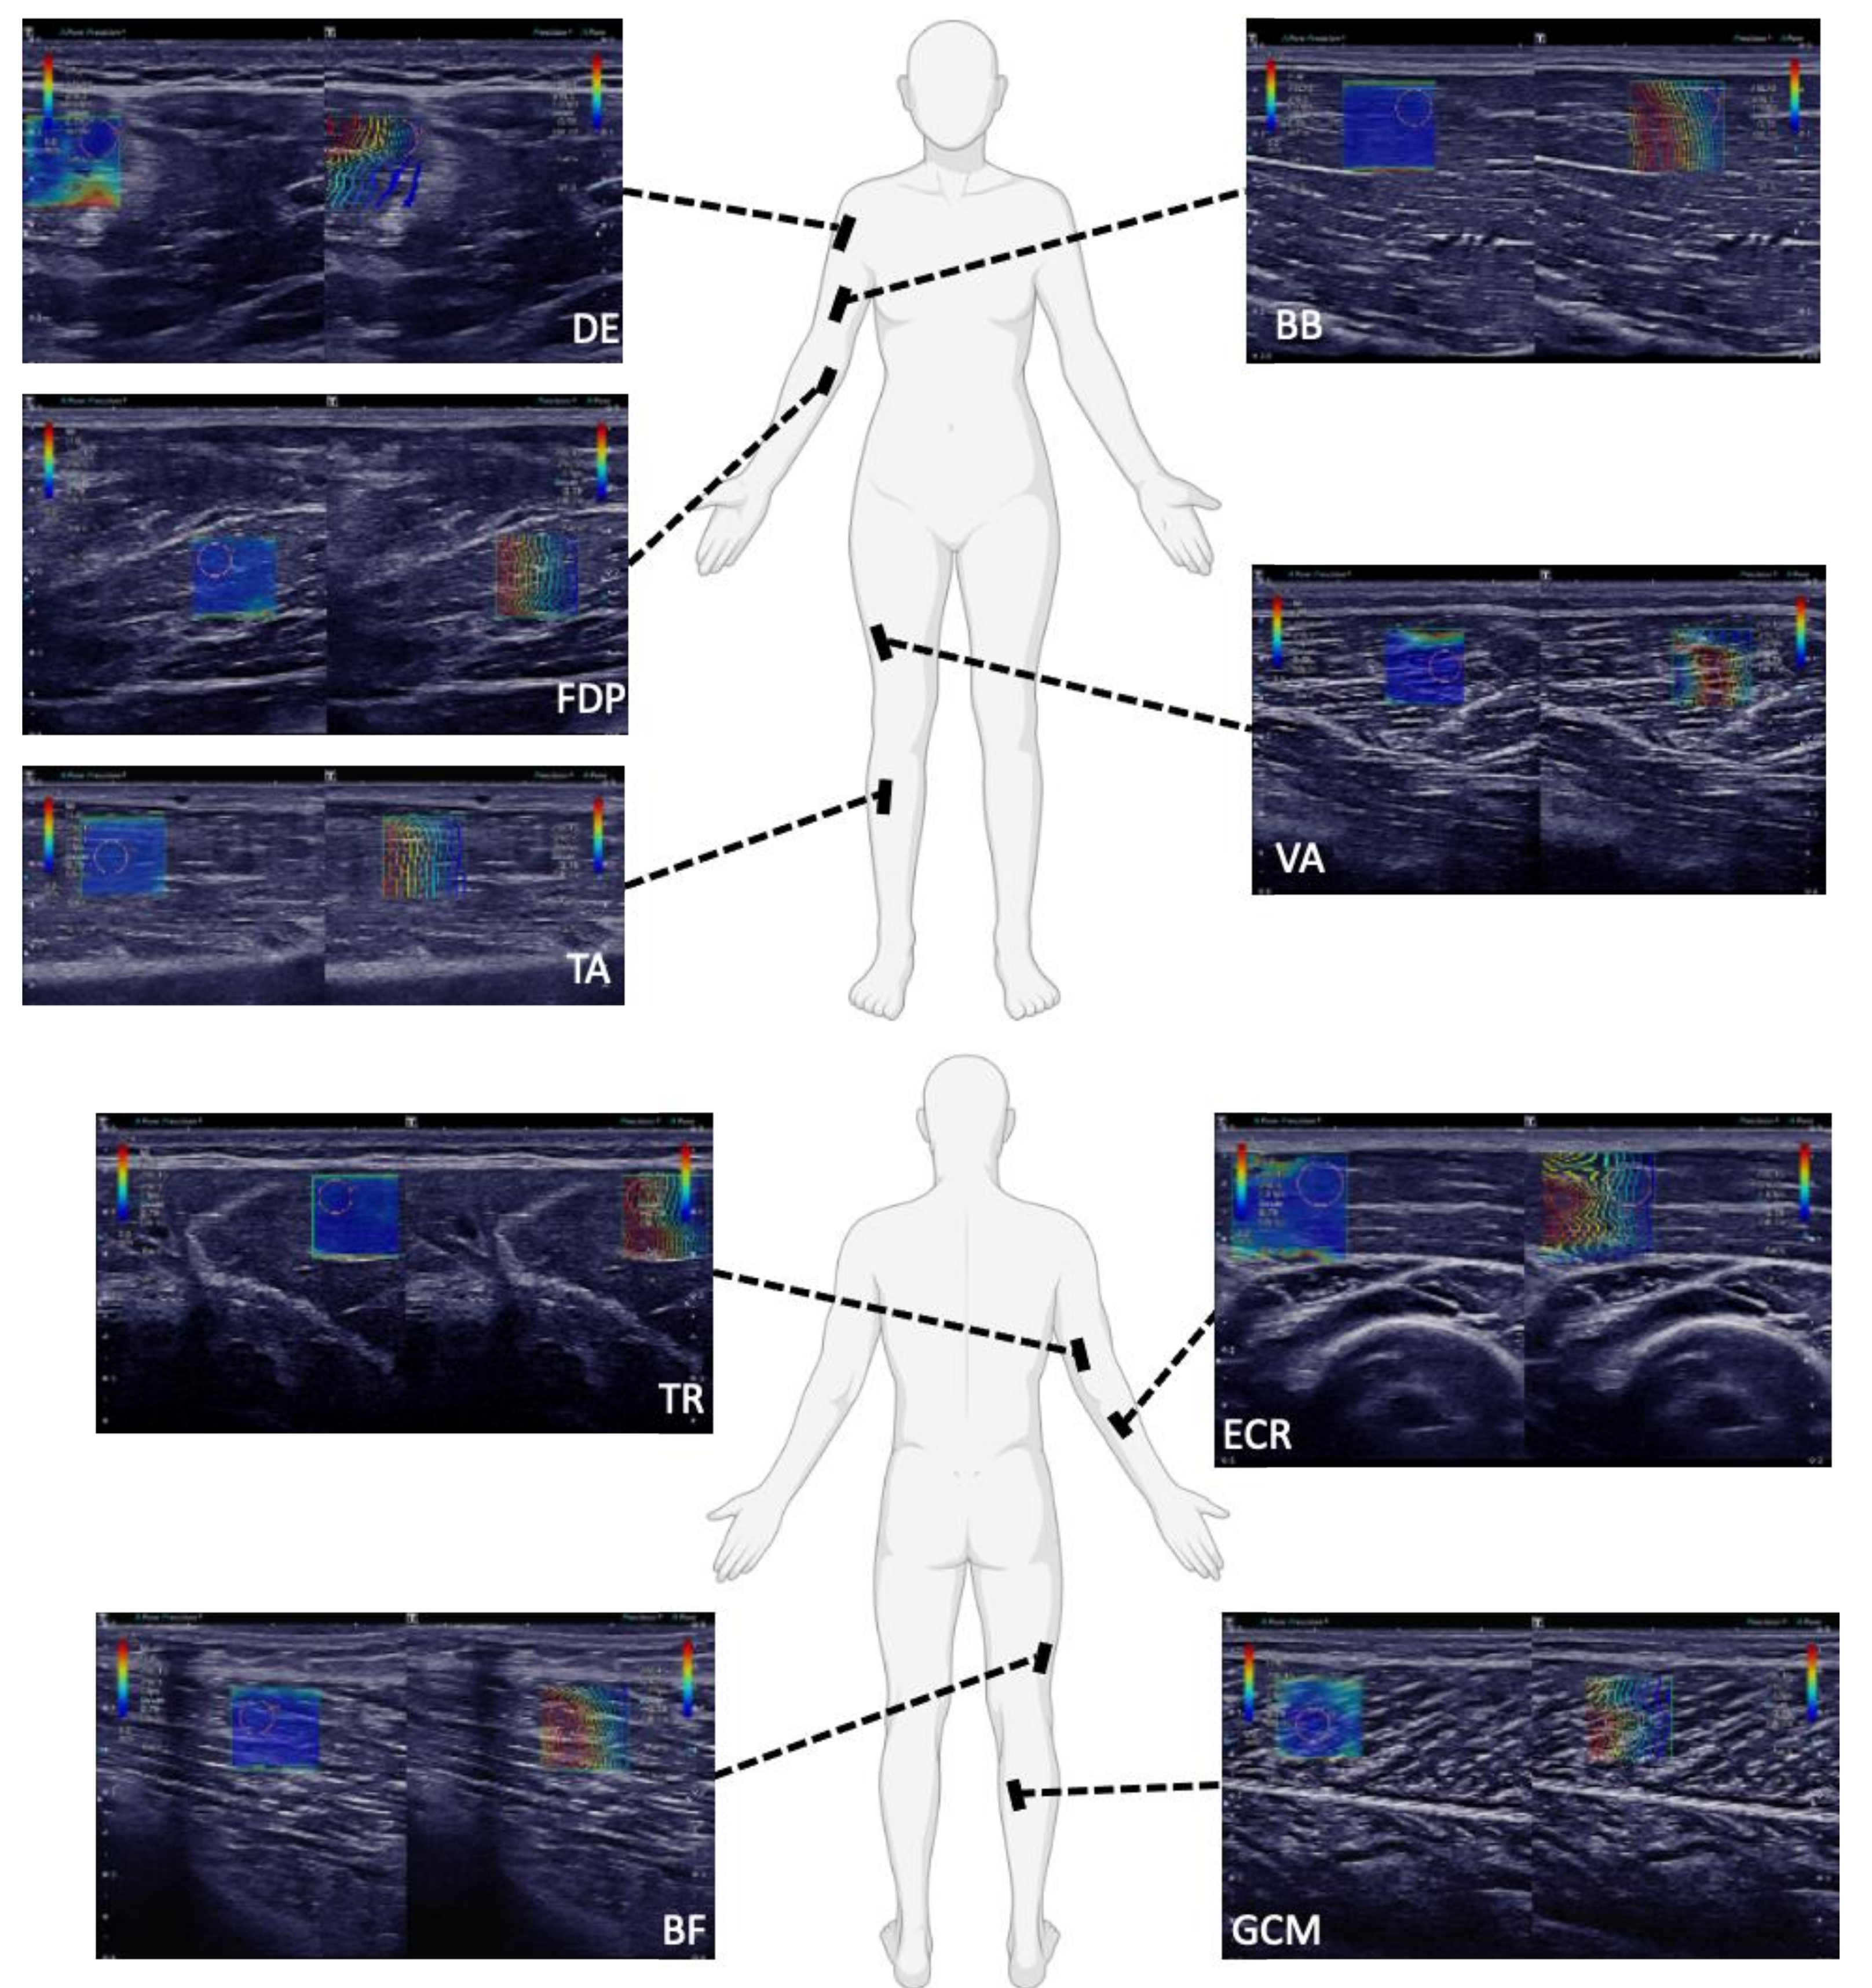

Figure A1.

SWE images of the examination of a 32-year-old male in Protocol 2 (optimized, rigid SWE-protocol): SWE pictures of the deltoid (DE), flexor digitorum profundus (FDP), tibialis anterior (TA), biceps brachii (BB) and vastus lateralis (VA) muscle, triceps brachii (TR), biceps femoris caput longum (BF), extensor carpi radialis (ECR) and gastrocnemius caput mediale (GCM) muscle are shown. On the left side of each picture, the B-mode images in gray scale are overlaid with SWV data in color. The cooler colors, such as the blue in these pictures, depict slower shear wave speeds, typically ranging from 0–6 m/s. As predicted, in Protocol 2 (optimized, rigid SWE-protocol), the muscles were positioned in optimally relaxed states, to avoid strain, which was demonstrated by the consistent blue coloring within the SWE pictures. On the right side of each picture, the shape of the shear waves is displayed with lines. The blue lines represent the origin of the shear waves and the red lines represent the change in the shear waves as they propagate accordingly through the muscle. In these pictures, the greater depth of acquisition required for FDP and DE can be seen. The layer of subcutaneous fat above the DE was typically thicker than for TA, BB and VA. Additionally, the greater pennation angle of DE is illustrated in that the muscle fibers could not be completely optimally displayed to parallel in the longitudinal plane. Alternatively, the path of the muscle fibers of FDP, TA, BB and VA could be displayed well in the longitudinal plane.